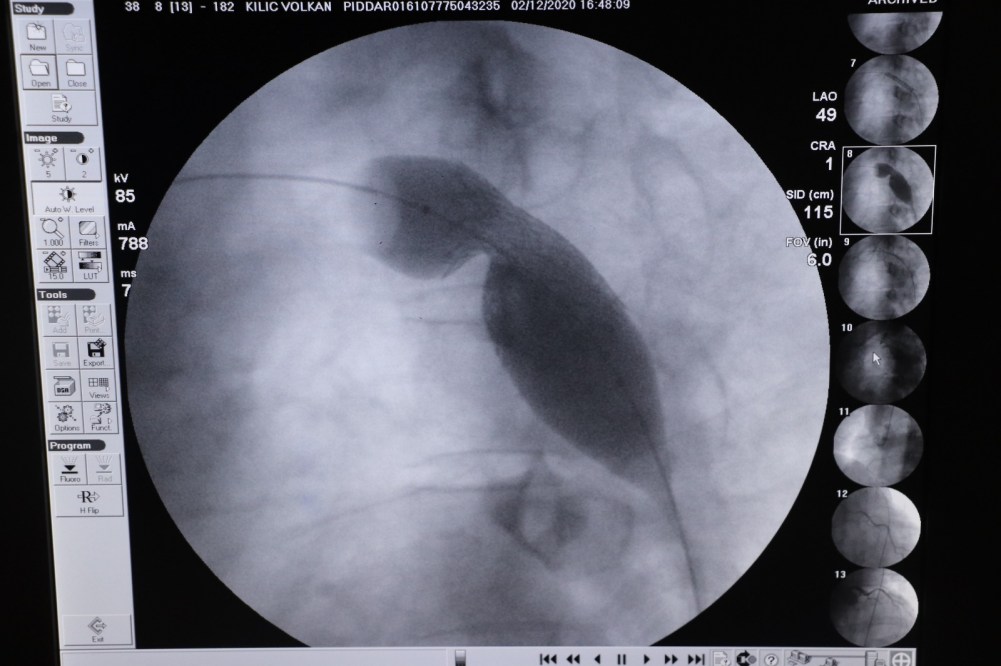

Son olarak geldiği Özel Echomar Hastanesi Doktorlarından Kardiyolog Doçent Doktor Mehmet Yaman’a muayene olan Volkan Kılıç’ın alpten çıkan aort damarının doğuştan dar olduğu tespit edildi. Yurt dışından getirtilen özel stentlerin Anjiyo yöntemi ile takılmasının ardından Volkan Kılıç’ın sağlığına kavuştuğu ifade edildi.

Yaman konuşmasında “Volkan kardeşimiz 39 yaşında erkek hastamız. Şimdiye kadar düşmeyen Hiper tansiyon şikâyeti ile hastanemize başvurdu. Yaptığımız tetkiklerde kalpten çıkan aort damarının doğuştan dar olduğunu tespit ettik. Çok nadir görülen bir konudur. 40 ve 50’li yaşlarda çok ciddi rahatsızlıklara neden olur. Birçok yandaş hastalıklara da neden olur bur hastalık. Gerekli tedavinin yapılamaması durumunda Beyin kanaması, kalp yetmezliği gibi ölümcül hastalıklara neden olur. Bunu tespit eder etmez müdahale ettik. Bu hastalığın iki ameliyat şekli var. Birisi kapalı diğeri açık ameliyat. Açık ameliyatta hastanın felç olma durumu söz konusuydu. O yüzden açık ameliyat çok önerilmiyor. Kapalı ameliyat ise özel stentlerle yapılıyor. Volkan bey stentlerini özel bir sipariş ile yurt dışından getirttirdik. İşlemi burada ameliyatsız Anjiyo yönetimi ile yaptık. Şu anda hiçbir sıkıntısı yok: Sağlığına kavuştu. Çok sıkıntıları olmuş. Ancak hayati bir sıkıntı yaşamamış olması, felç geçirmemiş veya ölmemiş olması kendisi için büyük bir şans” dedi.